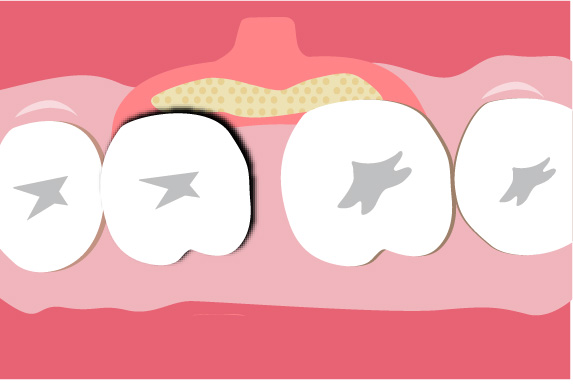

歯周組織再生療法は施術の難易度が高く、ほとんどの歯科では扱っていない内容です。